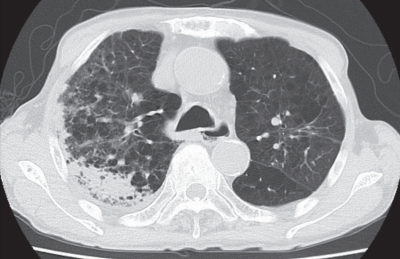

入院時の胸部エックス線写真と胸部単純 CTを別に示す。